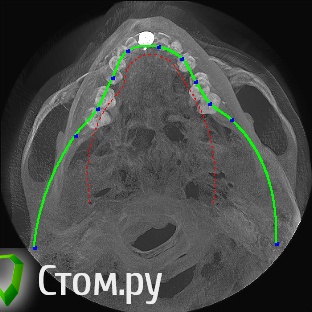

sergey765 Опубликовано 11 июня, 2014 Автор Поделиться Опубликовано 11 июня, 2014 посмотрите пожалуйста КТ. Ссылка на комментарий

sergey765 Опубликовано 11 июня, 2014 Автор Поделиться Опубликовано 11 июня, 2014 могу вам ещё снимков выложить.их довига. беспокаят меня боли после удаления .прошло 5 недель. снимки девушка лет 20 эти смотрела. сказала что у меня там инфекции дофига. типа давай я тебя на понедельник к хирургу запишу. он ранку вскроет. прочистит Ссылка на комментарий

Bier Опубликовано 11 июня, 2014 Поделиться Опубликовано 11 июня, 2014 это все не информативные кадры, в прикрепленных темах есть инструкция, выкладывайте КТ целиком, наш рентгенолог скачает и выложит срезы. 3 Ссылка на комментарий